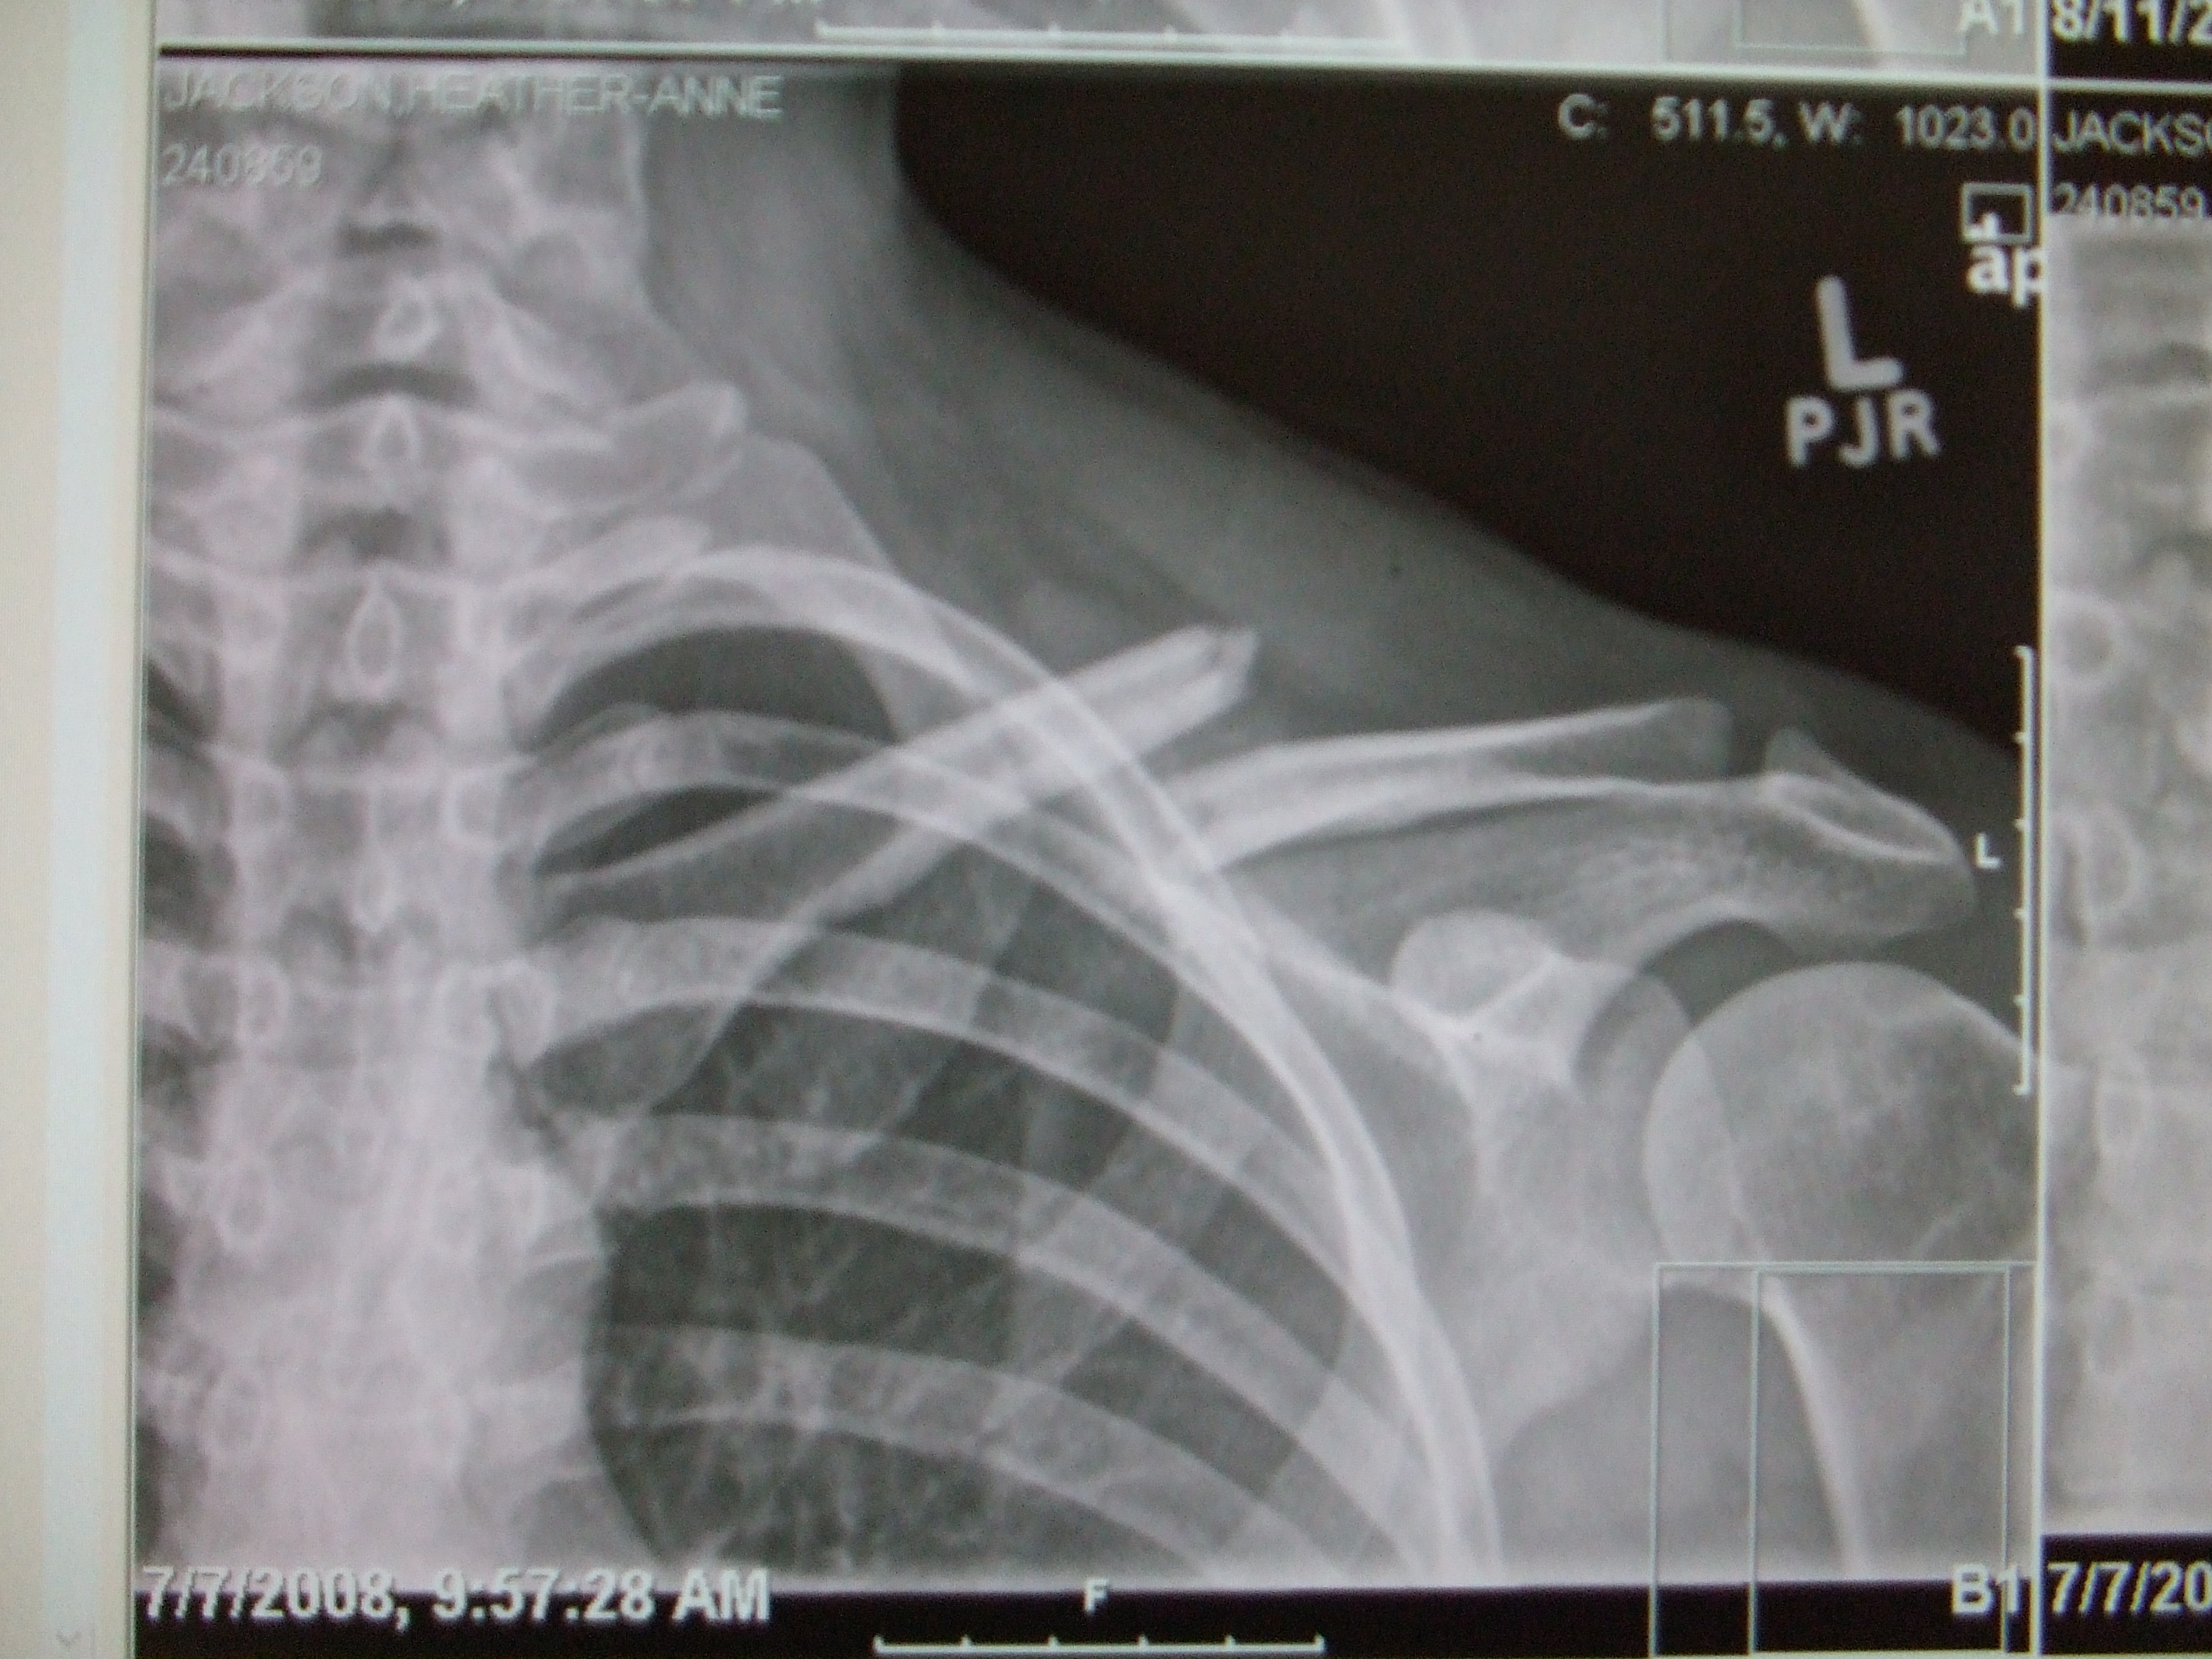

Ouchy2 005.jpg

part of Time (and medical attention) Heals All Wounds

Different Angle. 1 month after the initial break.